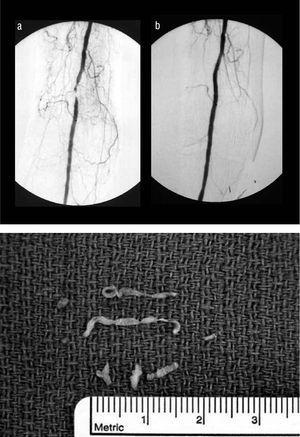

Fig. 1. Angiografía por sustracción digital que demuestra la oclusión total de la arteria poplítea proximal (A) y el resultado después de la aterectomía y la angioplastia adyuvante con balón (B). Tejido recuperado del catéter de aterectomía (C).

En el quirófano, se implantó percutáneamente una hoja de calibre 8 en la arteria femoral común derecha utilizando un abordaje anterógrado. La oclusión de la arteria poplítea se atravesó utilizando una guía Balance Middlewight de 0,36 mm (Guidant, Indianápolis, IN), que se avanzó a través de un catéter balón de 1,5 por 15 mm. Utilizando el catéter Silverhawk LS (Fox Hollow, Redwood City, CA) se efectuaron 8 pases de escisión con la recuperación de una cantidad significativa de tejido aterosclerótico. La disección residual se trató con un balón de 6 x 20 mm insuflado hasta 4 atmósferas durante 90 s. Al completar la angiografía, se demostró una estenosis residual menor del 10% (figs. 1B y 1C). La arteriotomía se cerró utilizando un Angio-Seal (St. Jude Medical, St. Paul, MN). A continuación, se efectuó un bypass del tronco tibioperoneo hasta la arteria tibial posterior inframaleolar con vena cefálica invertida. Tras el procedimiento de revascularización combinado, se identificó un pulso palpable en el injerto y una excelente señal Doppler de baja resistencia en la arteria tibial posterior más allá de la anastomosis distal. El paciente fue dado de alta 4 días después de este procedimiento. A las 4 semanas de seguimiento, el lugar de la amputación del segundo dedo del pie derecho había curado por completo.